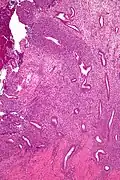

| Micrograph of a uterine adenosarcoma showing a mitotically active malignant stroma and benign glands. H&E stain. | |

Uterine adenosarcoma have, by definition, a malignant stroma and benign glandular elements. The World Health Organization (WHO) criteria have a mitotic rate cut point; however, this is often disregarded, as bland-appearing tumours with a low mitotic rate are known to metastasize occasionally.[2]